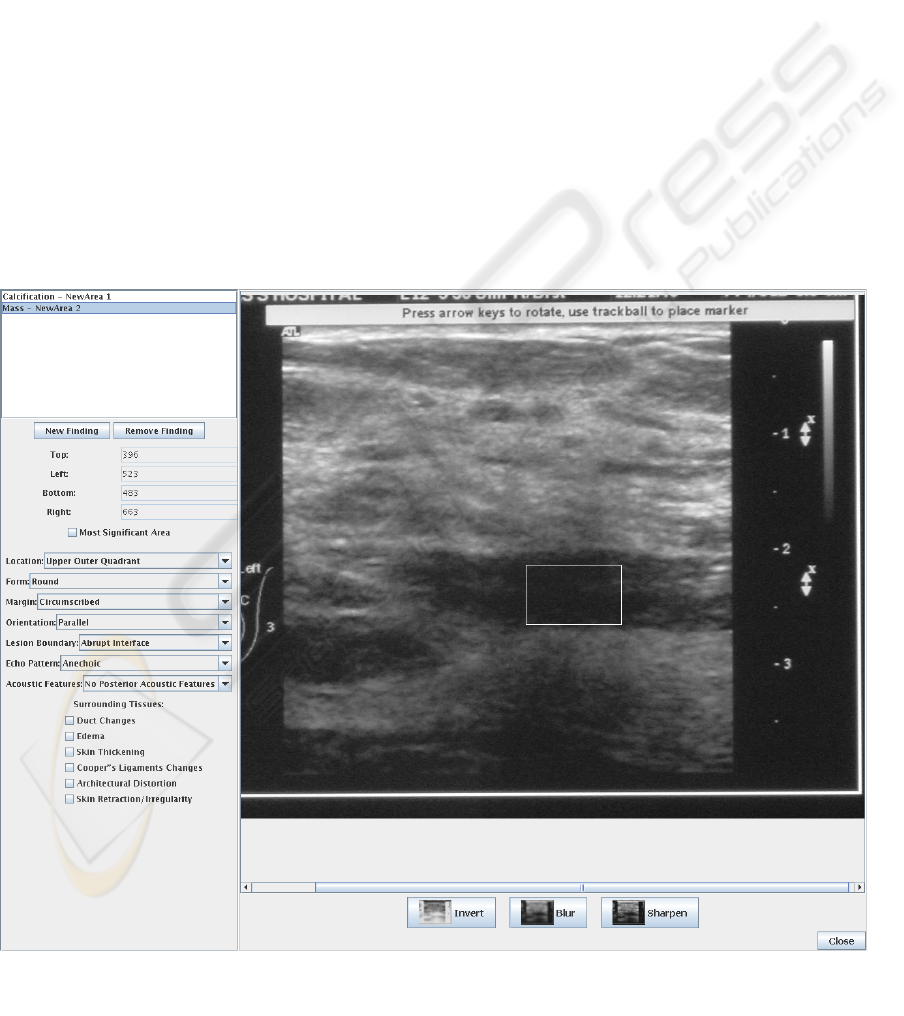

In this work, the focus is on breast imaging, but

advantages and pitfalls. Section 3 is dedicated to the

overall system architecture wherein a detailed

description of the major components will be given.